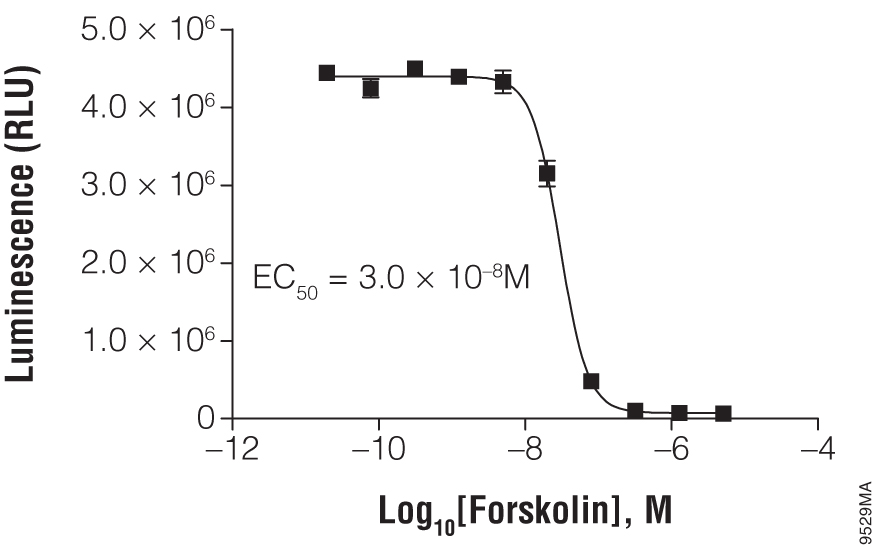

Measure Intracellular cAMP in Cell Lysates

The cAMP-Glo™ Max Assay is a sensitive, reproducible bioluminescent assay for measuring intracellular cAMP. Compatible with diverse samples and high-throughput formats, it offers extended signal stability and minimizes interference for reliable results.

Titration of forskolin using cAMP-Glo™ Max Assay. In a white, clear-bottom, 384-well plate, 2,000 HEK293 cells were exposed to the indicated concentration of forskolin.